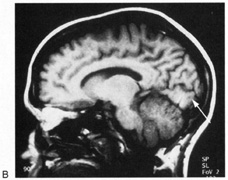

Fig. 18. Magnetic resonance imaging scan of patient with stroke causing a right hemiachromatopsia as well as partial superior quadrantanopia.

Achromatopsia in the contralateral hemifield alone can follow unilateral right or left occipital lesions (Fig. 18). Patients are typically asymptomatic until the defect is demonstrated on examination.234,235 Hemiachromatopsia is usually associated with a superior quadrantanopia;234,235,241 therefore, the color defect is only demonstrable in the remaining inferior quadrant. The preserved color vision in the ipsilateral hemifield allows normal or near-normal performance on centrally viewed tests of color vision such as pseudoisochromatic plates. The incidence of hemiachromatopsia is probably underestimated, given its asymptomatic nature and the failure of routine clinical color tests to detect its presence.

HEMIACHROMATOPSIA.